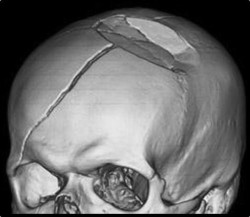

Nous trouvons quatre différents types de fractures crâniennes :

Fracture linéaire

C’est la plus fréquente. Elle se situe, la plupart du temps, sur les côtés du crâne. Une distance entre les os plus ou moins marquée peut être aussi notée.

Fracture croissante

Ce type de fracture est rare, mais nécessite une prise en charge rapide, puisqu’elle est croissante dû aux pulsations du liquide céphalo-rachidien. Elle se caractérise par un écartement de l’os de plus de 3 mm, une déchirure de la pellicule couvrant le cerveau et des contusions cérébrales. Un examen en échographie peut valider la déchirure de la dure-mère.

Fracture ping-pong

La fracture ping-pong se produit lors d’un impact avec un objet contondant. Une consultation en chirurgie est alors nécessaire.

Fracture de la base crânienne

Cette fracture est rare si les chutes ou les impacts sont de faible altitude. Il y a une atteinte du nerf crânien et une fissure du liquide céphalo-rachidien (liquide se trouvant dans la moelle épinière et le cerveau) est souvent probable.